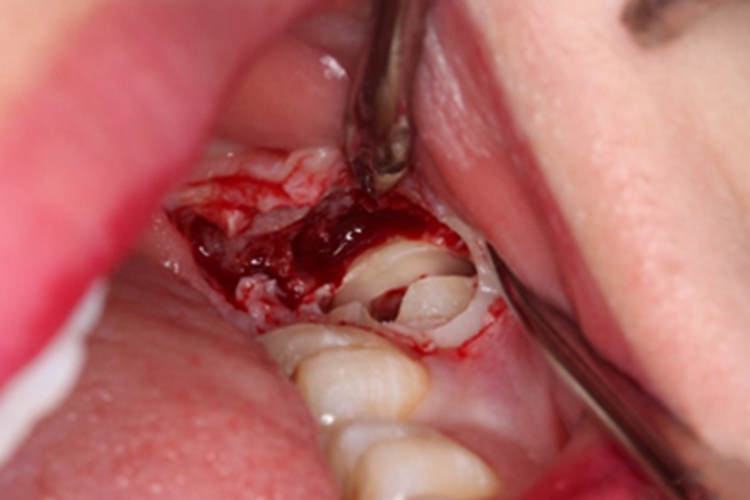

去骨并分牙

翻瓣后多采用高速涡轮机或其他动力系统去骨,将整块颊侧骨板去除,暴露牙体。然后将牙体劈开,分割牙冠和牙根,解除邻牙阻力。